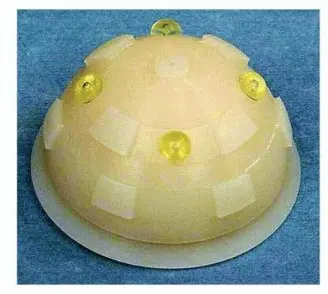

على الرغم من التوجه الحديث نحو استخدام الغرسات غير المثبتة بالإسمنت، إلا أن المكون الحقي المثبت بالإسمنت لا يزال يحتل مكانة مرموقة في العديد من المراكز الطبية حول العالم، بما في ذلك عيادة الأستاذ الدكتور محمد هطيف في صنعاء، وذلك بفضل نتائجه الممتازة ومعدلات بقائه العالية. يهدف استخدام الإسمنت في تثبيت المكون الحقي إلى تحقيق تداخل ميكانيكي قوي وواسع بين الإسمنت وعظم الحوض، مما يؤدي إلى واجهة مستقرة تعتمد على الاتصال المباشر بين الإسمنت والعظم الحي (الاندماج العظمي). هذه الواجهة تمثل أساسًا موثوقًا للاستقرار طويل الأمد للمفصل.

يتم استخدام مبشرة كهربائية في محور التجويف الحقي. يتم التوسيع المتتالي والمركز بهدف إزالة العظم تحت الغضروفي وكشف العظم الإسفنجي الذي يمكن ضغط إسمنت البولي ميثيل ميثاكريلات (PMMA) فيه. تُستخدم المبشرة بزيادات 2 ملم. الجدار الأمامي هو الأكثر عرضة للترقق المفرط، لذلك يتم وضع المبشرة قليلاً إلى الخلف. يتوقف التوسيع عندما يتم تنظيف حافة التجويف الحقي لكشف العظم الإسفنجي النازف.

تحديد حجم المكون التجريبي

عادةً ما يكون التجويف بقطر 2 ملم أصغر من أكبر مبشرة مستخدمة هو الغرسة ذات الحجم المناسب. يتم وضع الحافة التجريبية على أداة الإدخال مع الكوب التجريبي، ويتم قص الحافة على طول الخط الذي يشير إلى أكبر مبشرة مستخدمة. ثم يتم إعادة وضع الكوب التجريبي داخل التجويف الحقي وتقليم الحافة مرة أخرى، إذا لزم الأمر، بحيث تقع داخل فتحة التجويف الحقي مباشرة.

تحضير المكون النهائي

يتم بعد ذلك تقليم حافة المكون النهائي باستخدام الحافة التجريبية. يتم التدرب على الوضع المناسب للمكون داخل التجويف الحقي.

يُطبق الإسمنت في التجويف الحقي بعد حوالي ثلاث دقائق ونصف من الخلط، مع التأكد من إزالة أي كتلة زائدة. قد تختلف التوقيتات قليلاً حسب نوع الإسمنت المستخدم.

ضغط الإسمنت

يتم الضغط على الإسمنت باستخدام قرص سوربوثان (sorbothane disc) يمكن التخلص منه بالحجم المناسب، مما يضمن إغلاقًا جيدًا عند حافة التجويف. يتم تطبيق قوة كبيرة لدفع الإسمنت إلى العظم ويتم الحفاظ على الضغط لتقليل خطر النزيف الراجع من عظم المضيف. يساعد جهاز الشفط في تقليل أي نزيف راجع.

تتم إزالة أداة الضغط وتنظيف سطح الإسمنت من أي دم بمسحة. يتم تطبيق المزيد من الإسمنت في التجويف الحقي إذا لزم الأمر.